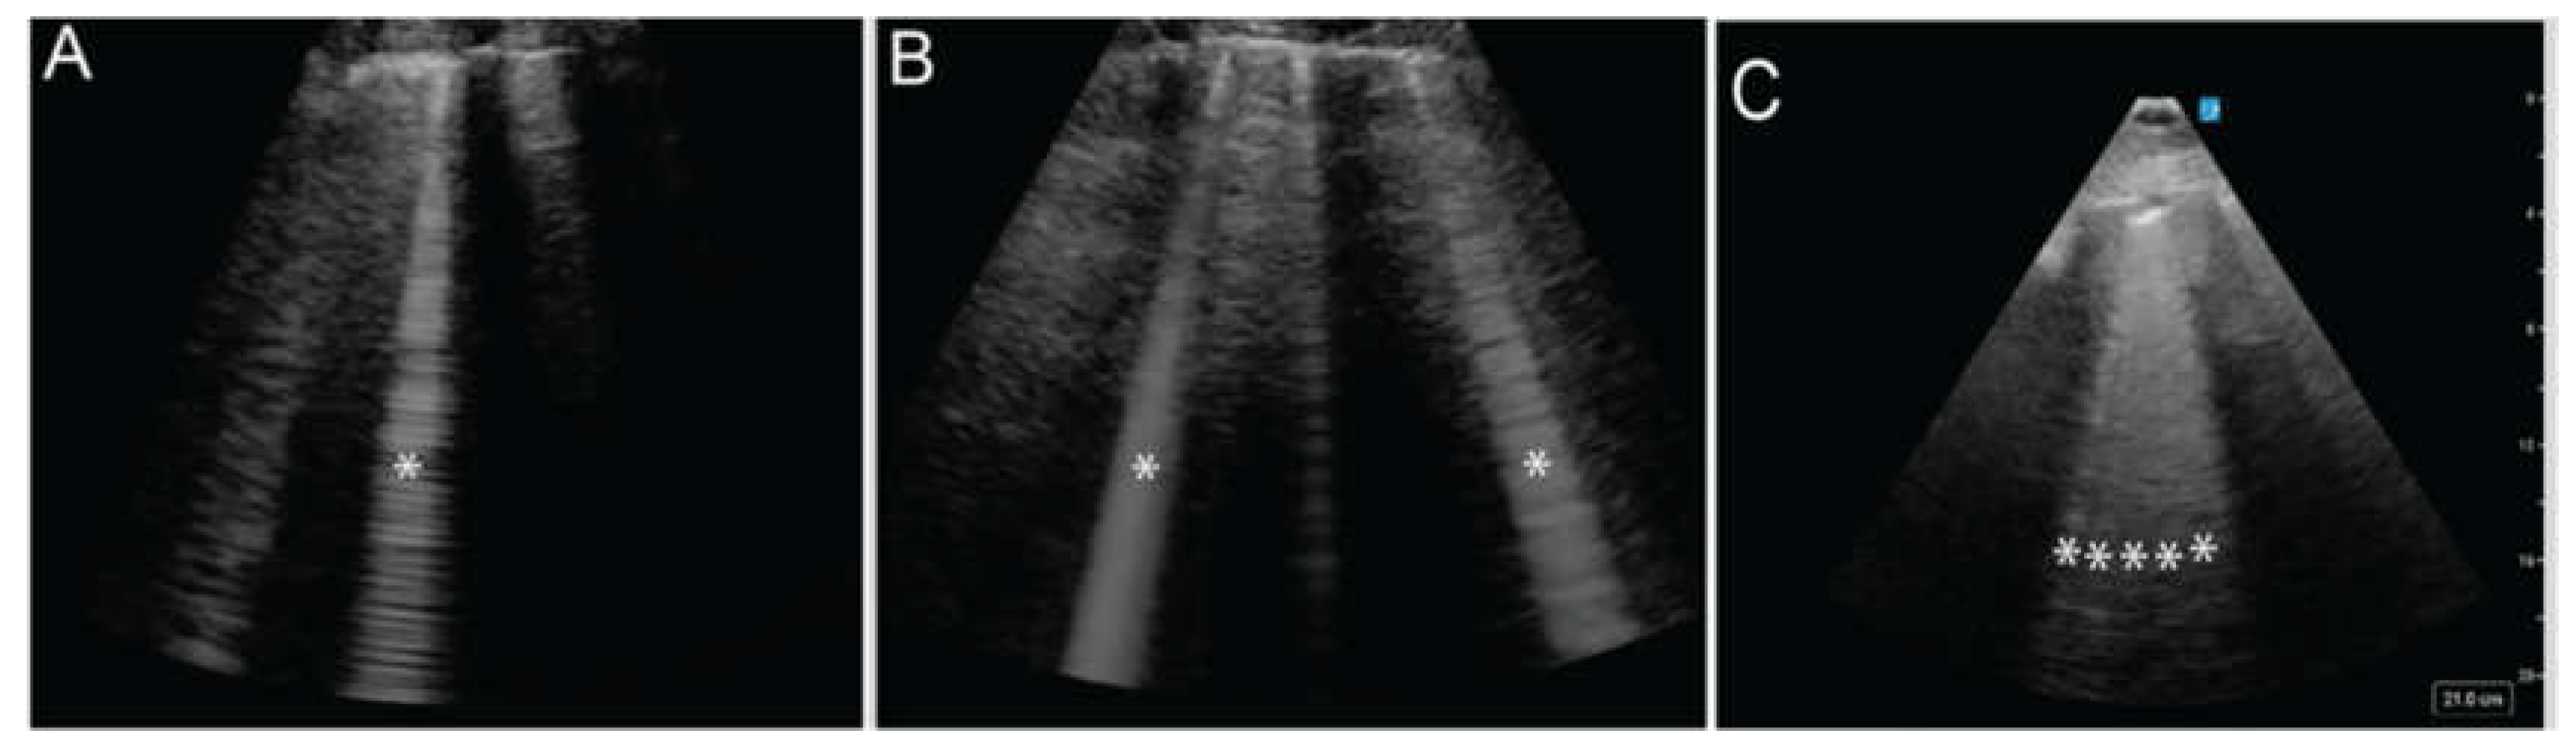

B Lines

B-lines are vertical, hyperechoic artifacts that extend from the pleural line to the maximum image depth, move with lung sliding, and obliterate A-lines (Video 2) [18]. They indicate a process of irregular alveolar filling where some alveoli are inflated with air while others are filled with fluid, purulent material, or inflammatory byproducts. Isolated, scattered vertical lines (Figure 5A) are considered normal, while 3 or more B-lines within a single window are considered abnormal and described as alveolar-interstitial syndrome. The greater the disruption of the pleural surface by B-lines, the more severe the underlying pathology is likely to be (Figure 5 A, B, C). This pattern is found in 100% of patients with acute cardiogenic pulmonary edema but only 8% of those with COPD exacerbations, making ultrasound a valuable tool for distinguishing between these conditions [19,20].

Figure 5. The * indicates vertical, hyperechoic artifacts extending from the pleural line. The increasing number of these artifacts represent B-lines in panels B, and C suggests a progression of lung interstitial fluid accumulation.